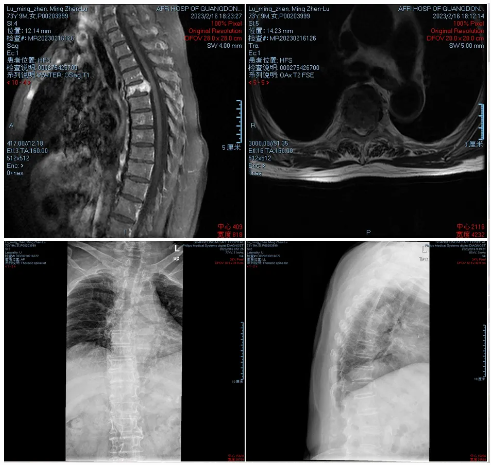

·患者陆某某,女,73岁,因反复胸背部疼痛1年余入院。胸背痛VAS评分7分。

·诊断:胸4椎体浆细胞骨髓瘤

射频消融治疗后疼痛缓解明显,术后第二天即可佩戴腰围起床活动,胸背痛VAS评分2分。